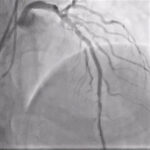

Η διάνοιξη χρόνιων ολικών αποφράξεων αποτελεί μία από τις πιο απαιτητικές και εξειδικευμένες παρεμβάσεις στον τομέα της επεμβατικής καρδιολογίας. Αναφέρεται στην προσπάθεια αποκατάστασης της αιματικής ροής στεφανιαίων αρτηριών που έχουν πλήρως αποφραχθεί για διάστημα μεγαλύτερο των τριών μηνών.

Παρά τις τεχνικές δυσκολίες, οι σύγχρονες τεχνικές και η εμπειρία των εξειδικευμένων καρδιολόγων έχουν αυξήσει σημαντικά τα ποσοστά επιτυχίας, προσφέροντας ανακούφιση από τα συμπτώματα και βελτίωση της καρδιακής λειτουργίας.

Οι χρόνιες ολικές αποφράξεις των στεφανιαίων αγγείων αποτελούν την πιο προχωρημένη εκδήλωση της στεφανιαίας νόσου. Πρόκειται για πλήρη απόφραξη μιας στεφανιαίας αρτηρίας που διαρκεί περισσότερο από τρεις μήνες. Αυτό έχει ως αποτέλεσμα την  πλήρη διακοπή της ροής αίματος.

Το ισχαιμικό τμήμα του μυοκαρδίου αιματώνεται παθητικά μέσω παράπλευρων αγγειακών κλάδων, οι οποίοι επαρκούν για τη διατήρηση της ζωής του ιστού, όχι όμως και για την πλήρη κάλυψη των μεταβολικών του αναγκών, ιδίως κατά την άσκηση.